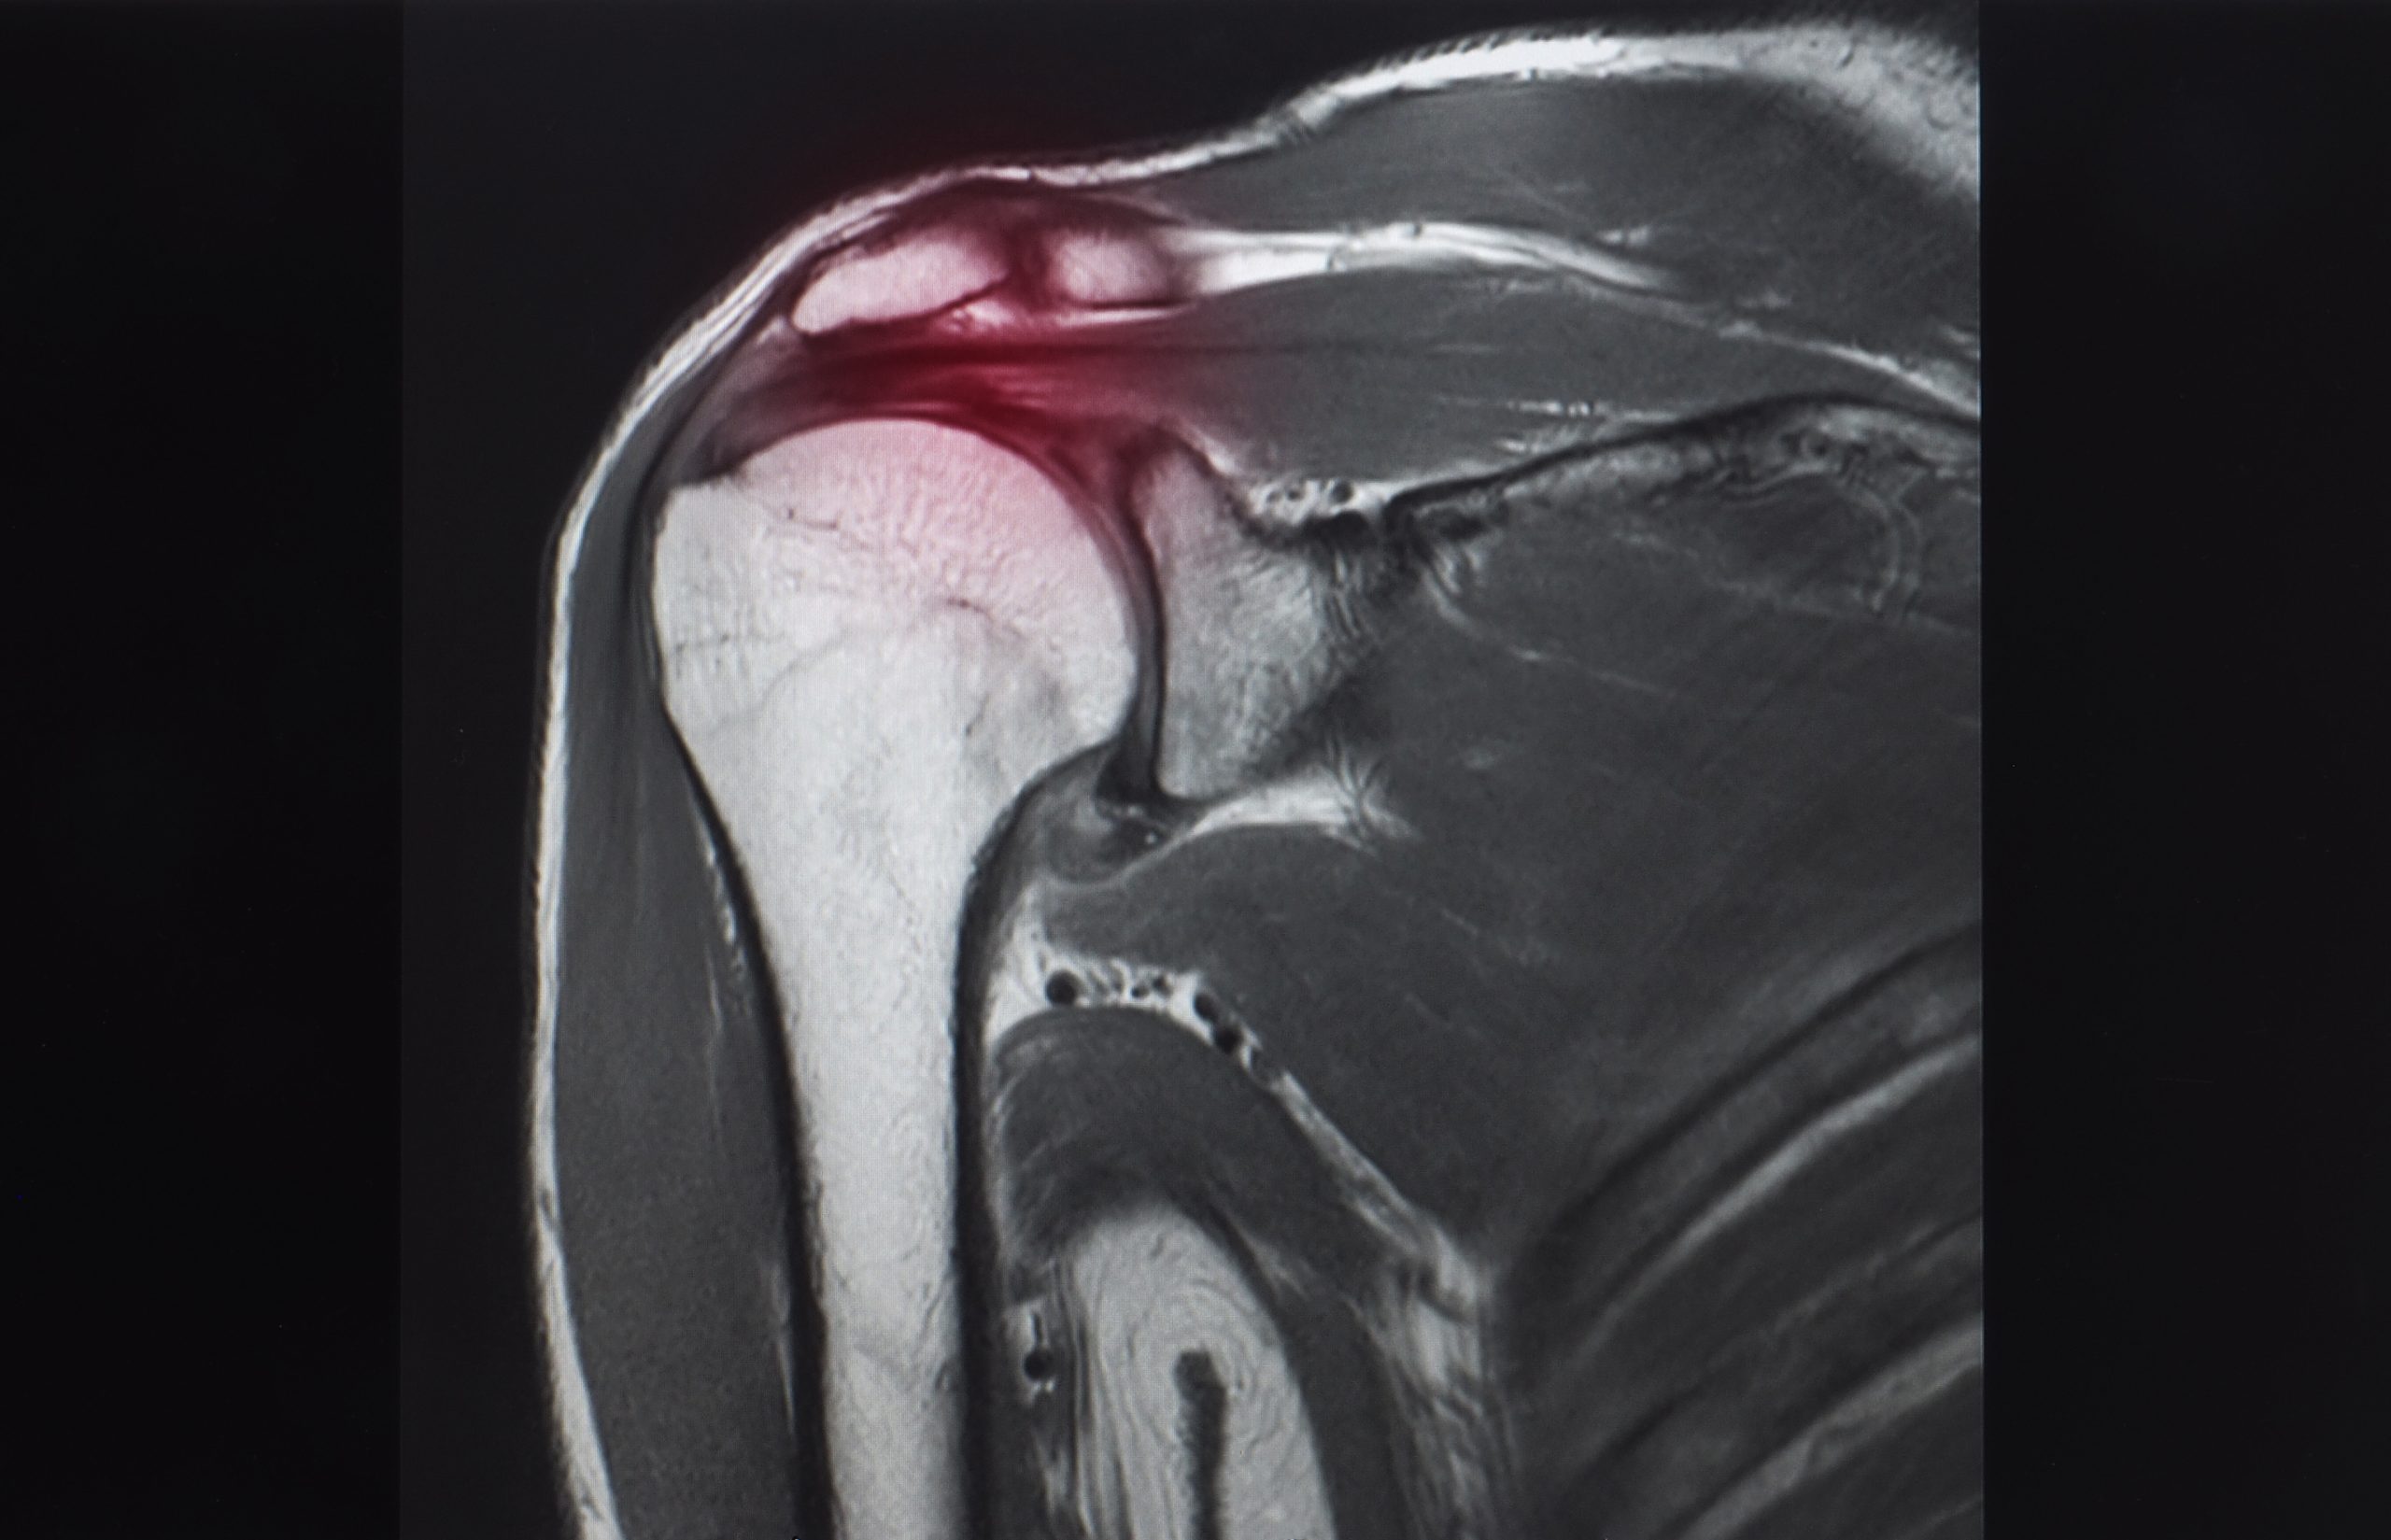

Diagnosing calcific tendonitis typically begins with a clinical diagnosis based on symptoms and physical examination, but imaging studies are required for confirmation. Healthcare providers may use X-rays to identify calcific deposits in the tendons, including both large and small calcific deposits. Magnetic resonance imaging is particularly useful for evaluating calcific deposits and associated tendon pathology, while ultrasound is effective for detecting small calcific deposits. Imaging can also reveal the resting phase of the disease, where calcific deposits appear homogeneously dense and chalk-like on radiographs. A detailed medical history and symptom review are essential for accurate diagnosis and treatment planning.